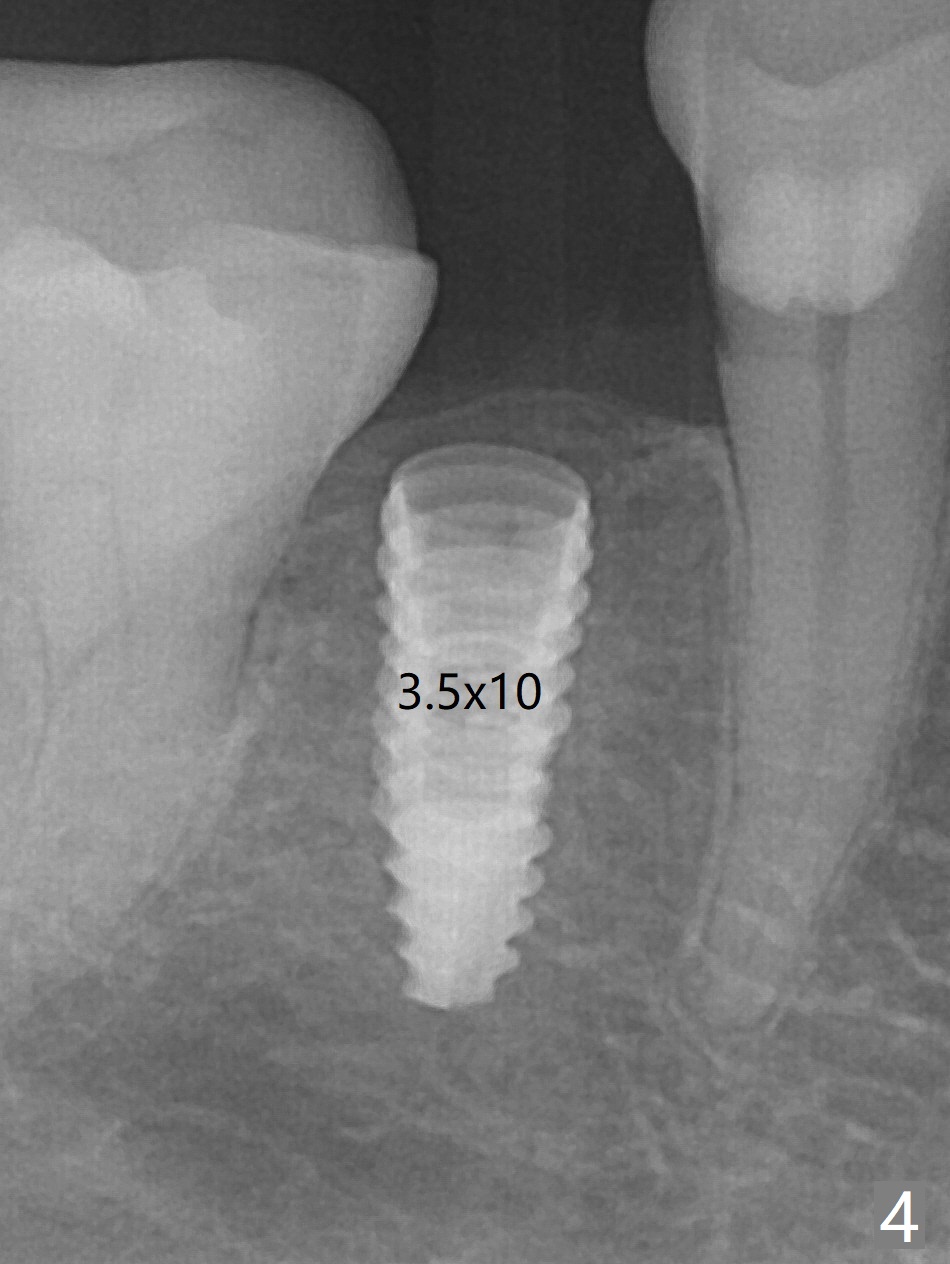

After incision the ridge at #29 is not so narrow as shown in Fig.1. But it is still intact, in contrast to what CBCT shows. Osteotomy is initiated with 1.2 mm drill, followed by 1/1.6, 1.3/2.3 and 1.7/3.1 mm DIO Bone Expanders. In fact mesial and distal crestal slots (BEB: bone expansion and bending) are created by using surgical fissure bur in order to insert the last bone expander in place (10 mm, Fig.2). Following 3.5 mm Cortical Tap, a 3.5x10 mm IS Implant is placed ~ 50 Ncm with clearance from the Mental Loop (Fig.3,4 red dashed line) and slightly subcrestal (Fig.5). The most distal part of the distal slot created for BEB is shown in Fig.5 *. Bone resorption is minimal 4 months postop (Fig.6,7). The implant was apparently placed in the middle buccolingually (Fig.8).